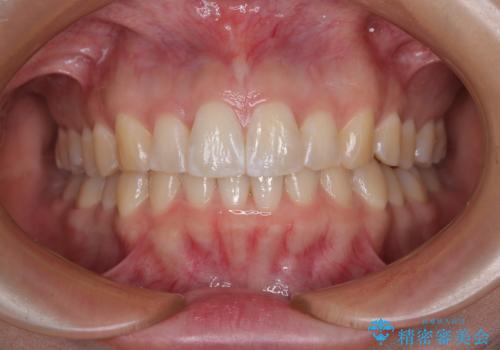

前歯のデコボコを治したい ワイヤー装置での非抜歯矯正

担当医 藤巻太一朗